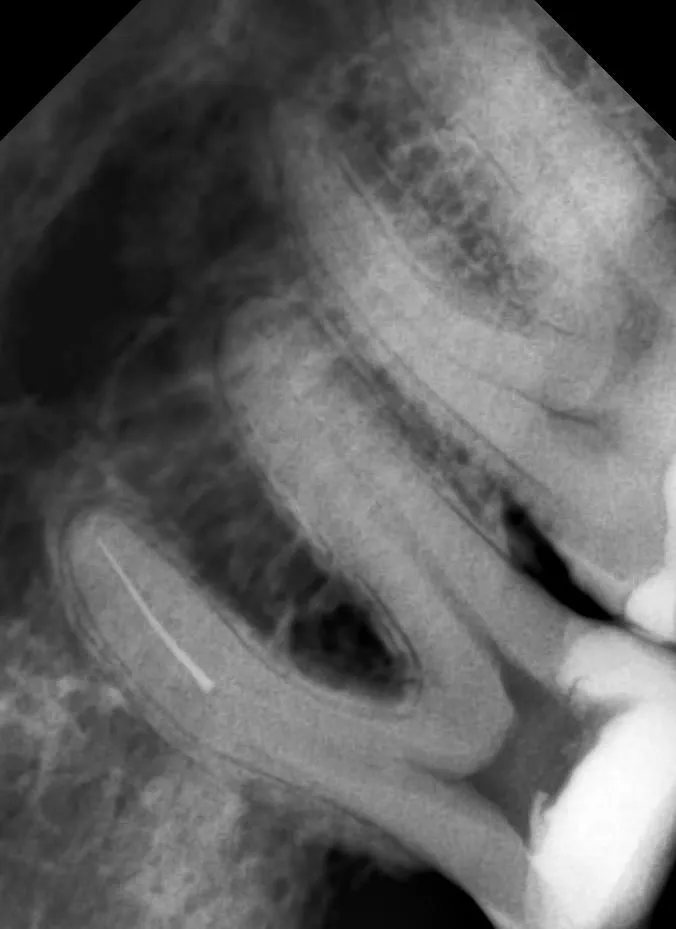

Пациент был направлен на приём после осложнения во время эндодонтического лечения: в корневом канале произошёл отлом инструмента. Самостоятельно извлечь фрагмент не удалось, поэтому было принято решение передать случай более узкому специалисту.

С учётом клинической ситуации выбран микроскопический метод извлечения. В ходе процедуры инструмент был аккуратно удалён, проходимость канала восстановлена.